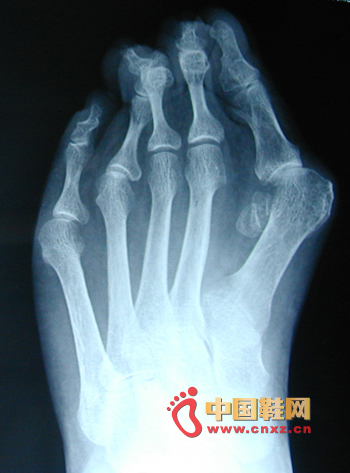

引起拇外翻的原因有哪些?拇外翻是常見的腳部畸形,也是眾多愛穿高跟鞋的女性的通病。調查發現,各個年齡段的女性都有拇外翻的發生,以20---60歲女性較為多見,而男性患者卻僅有女性患者的1/50的數量。所謂拇外翻,就是指拇趾向外偏離第一跖骨及拇趾通過關節的縱軸線,局部形成向內大于20度較的成角畸形。導致拇外翻的原因較多,如遺傳、扁平足,經常穿高跟尖頭鞋,造成拇趾過分外翻,無法正常穿鞋和行走。對于出現這樣的原因,除了是由于高跟鞋使女性身體的重力強行集中到一點以外,老年女性因為其體內的雌激素水平發生了變化,且韌帶的柔韌性減弱,也容易引發足骨增生,從而造成拇外翻。